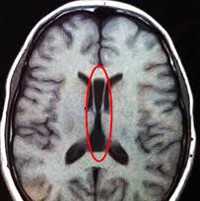

Диагноз уточняется на основании данных КТ и МРТ, при этом проводится серия снимков, подтверждающих наличие костного дефекта и присутствие мозговых тканей в выпячивании. Просвечивание (трансиллюминация) позволяет заподозрить наличие в образовании нервных тканей. Кроме того, даже легкое надавливание вызывает беспокойство пациента в связи с резким повышением внутричерепного давления.

Энцефалоцеле — пролабирование церебральных тканей и оболочек через дефект костей черепа, обусловленный его незаращением. Как правило, формируется по средней линии, но бывает и асимметричным. Небольшое энцефалоцеле может имитировать кефалогематому. В таких случаях определить диагноз помогает рентгенография черепа. Прогноз зависит от размеров и содержимого энцефалоцеле. При небольших размерах выпячивания и наличии в его полости эктопированной нервной ткани эффективно хирургическое удаление энцефалоцеле.

Одним из методов выявления пороков головного мозга у грудничков является нейросонография через родничок. Намного более точные данные у детей любого возраста и у взрослых получают при помощи МРТ головного мозга. МРТ позволяет определить характер и локализацию аномалии, размеры кист, гетеротопий и других аномальных участков, провести дифференциальную диагностику с гипоксическими, травматическими, опухолевыми, инфекционными поражениями мозга. Диагностика судорожного синдрома и подбор антиконвульсантной терапии осуществляется при помощи ЭЭГ, а также пролонгированного ЭЭГ-видеомониторинга. При наличии семейных случаев церебральных аномалий может быть полезна консультация генетика с проведением генеалогического исследования и ДНК-анализа. С целью выявления сочетанных аномалий проводится обследование соматических органов: УЗИ сердца, УЗИ брюшной полости, рентгенография органов грудной полости, УЗИ почек и пр.